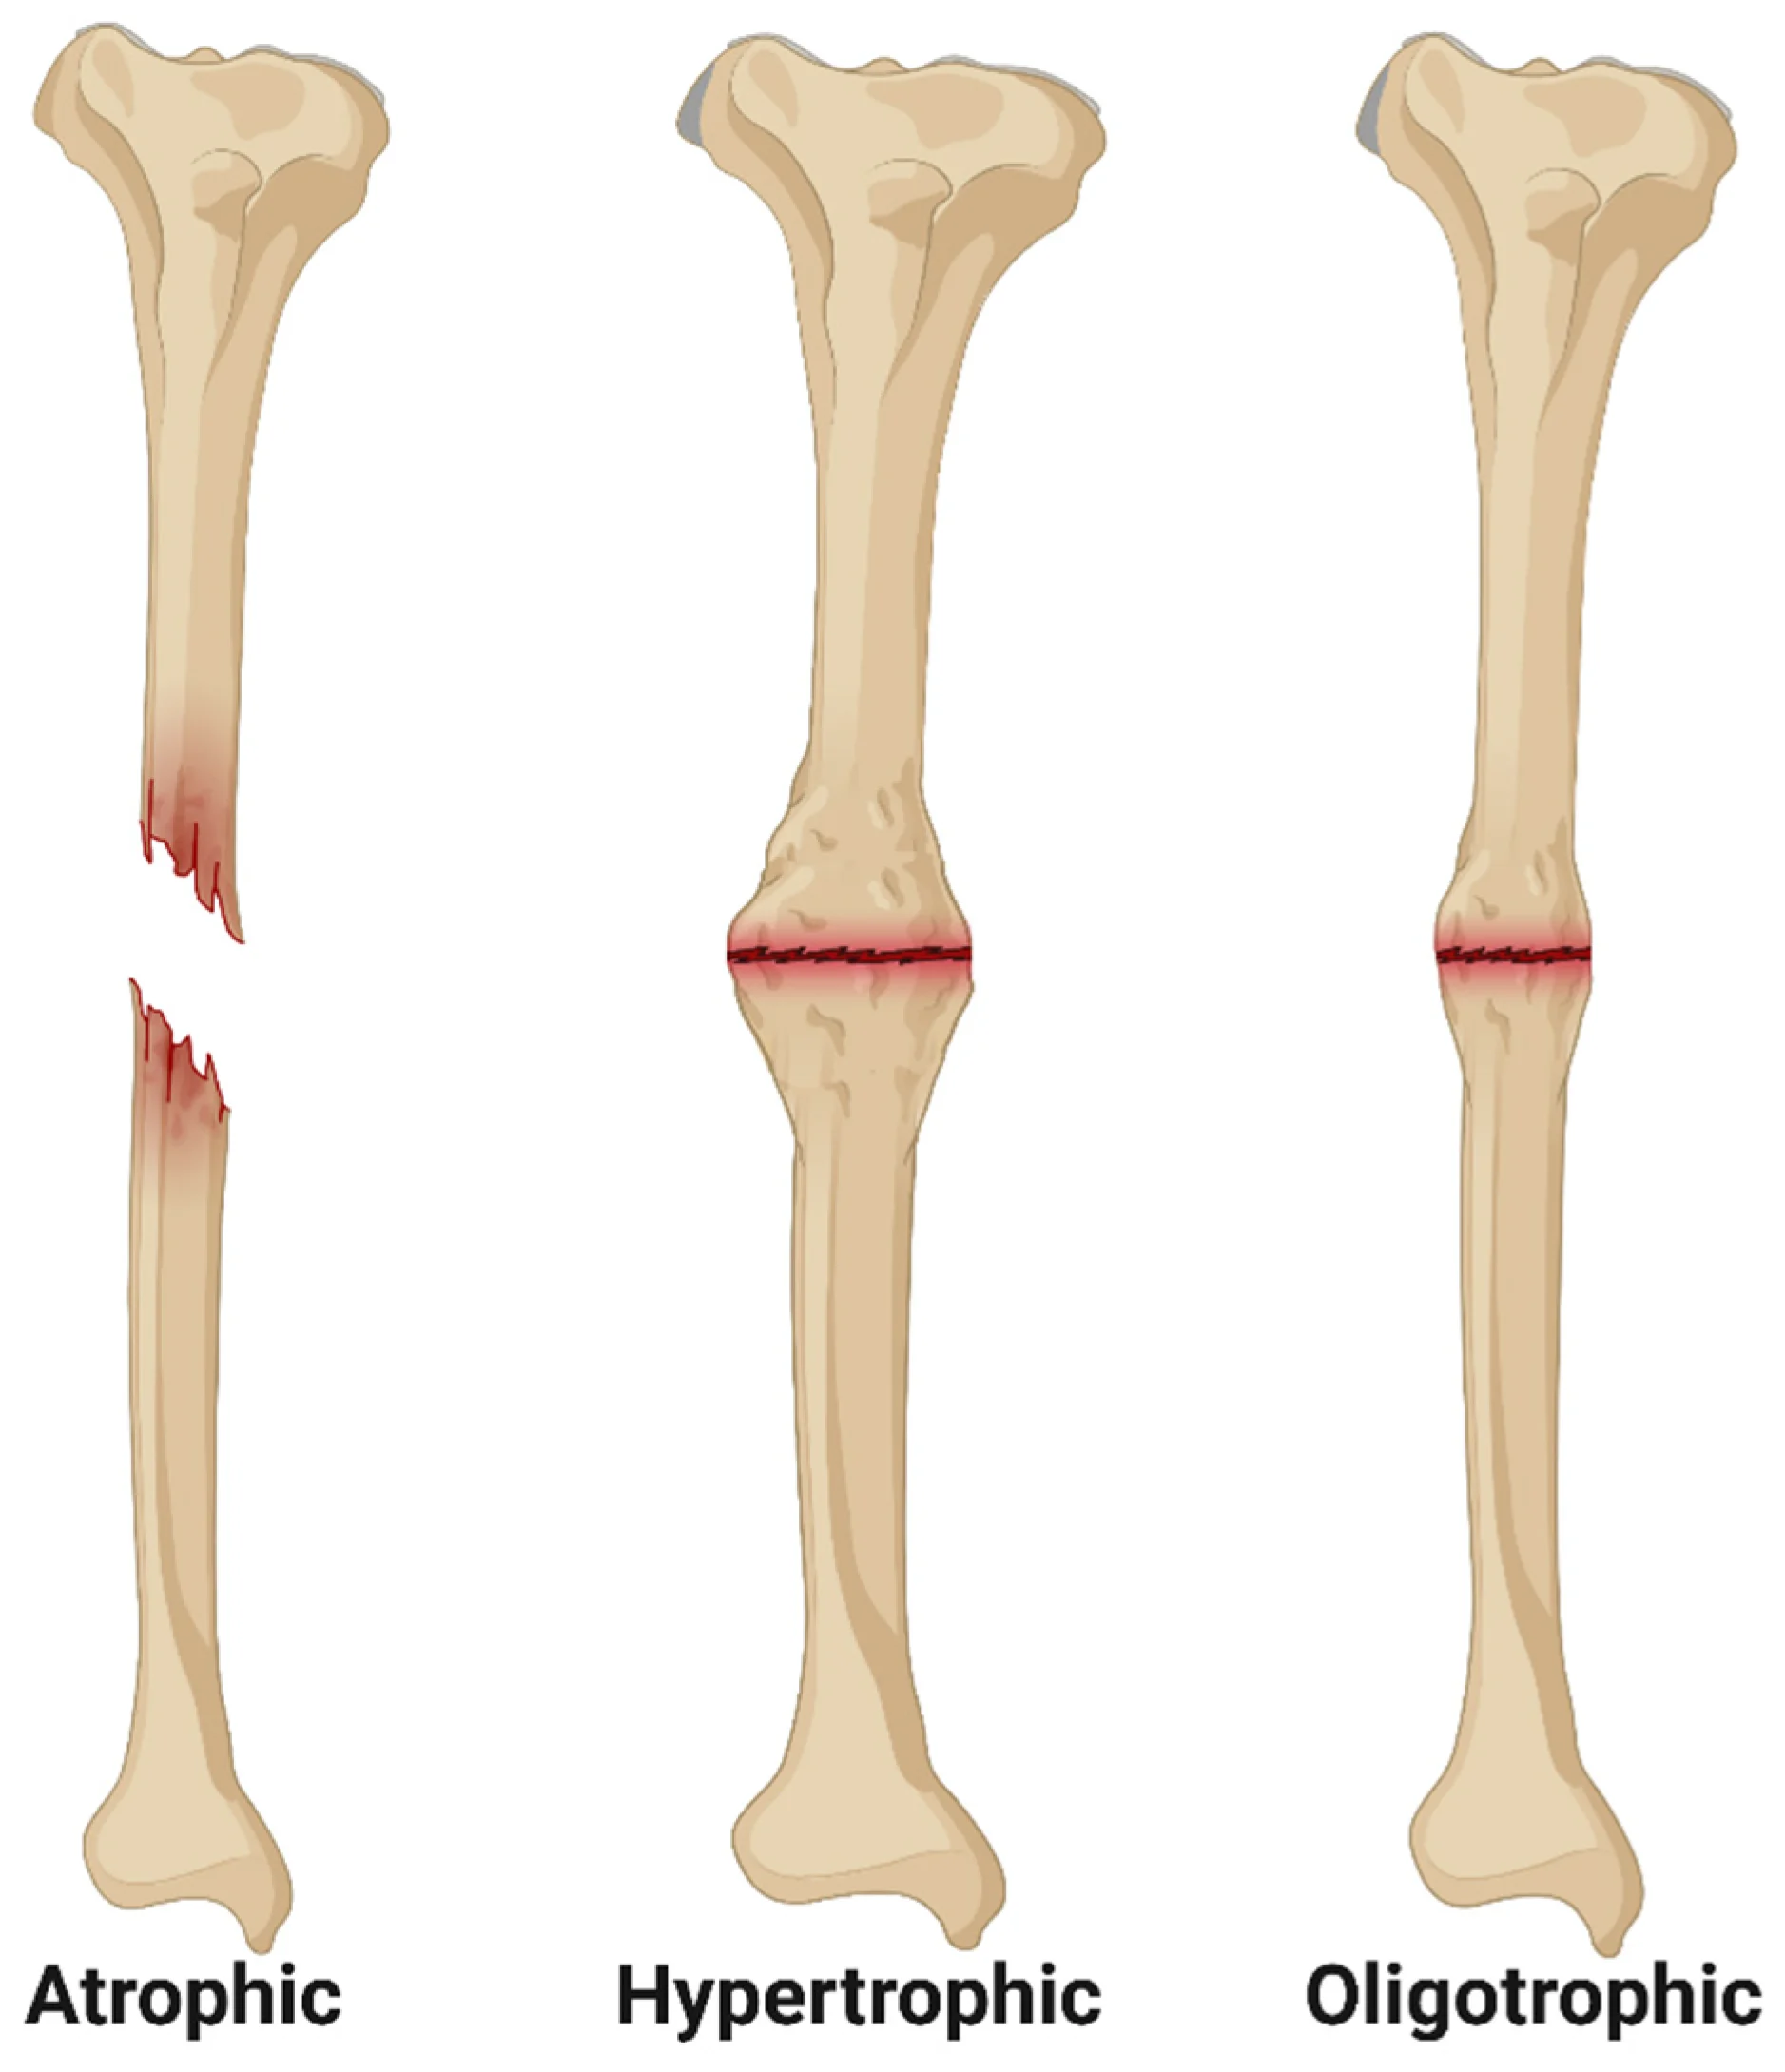

Non-Union & Mal-Union Fractures

Improperly healed fractures needing corrective treatment.